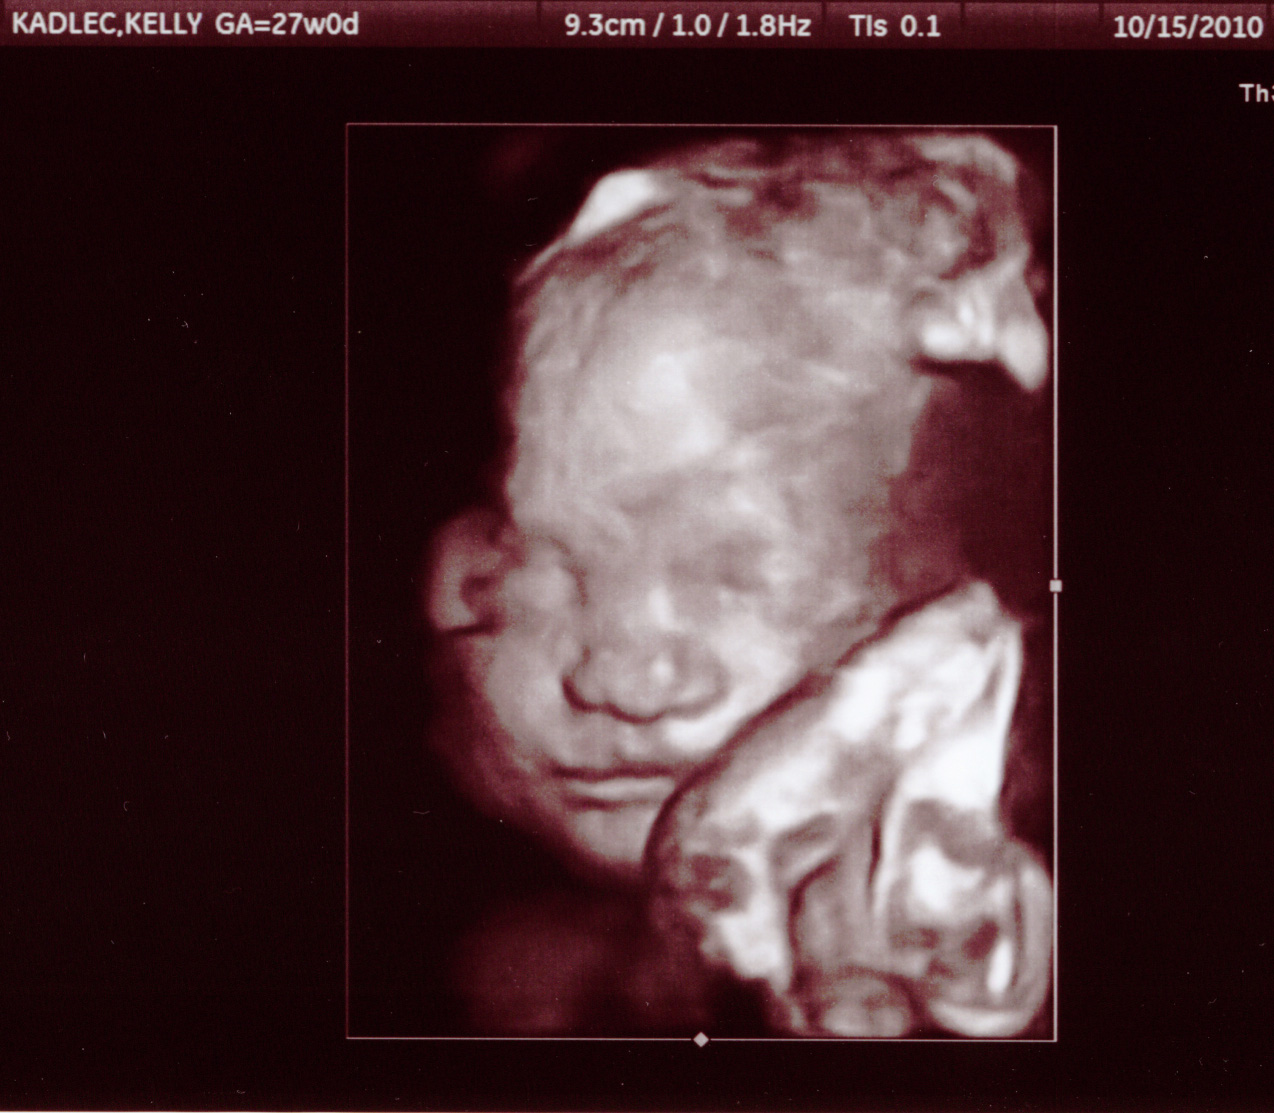

Here are some pictures from our 27 week appointment.